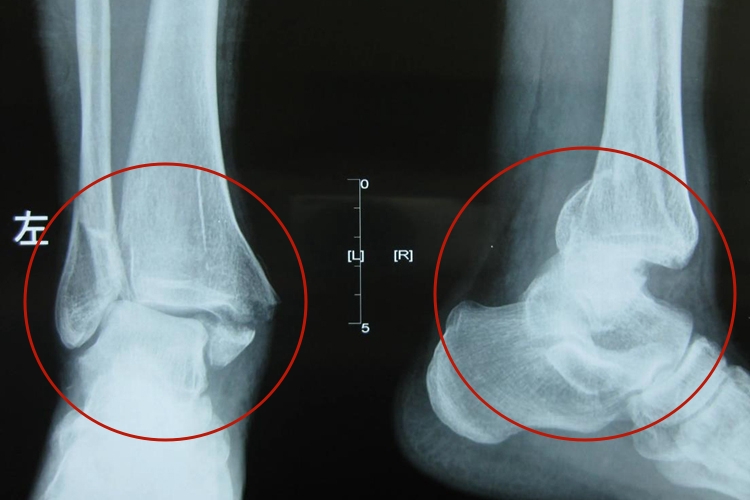

三踝骨折即内踝、外踝、后踝同时发生骨折,为踝部骨折分度中的Ⅲ度,同时伴有肿胀、疼痛、畸形等症状。可进行手法复位。

三踝骨折为暴力较大时,在内外踝骨折的同时,距骨向后撞击胫骨后缘或后踝,发生后踝骨折。骨折后局部肿胀、疼痛、淤斑、踝关节畸形,同时发生功能障碍。